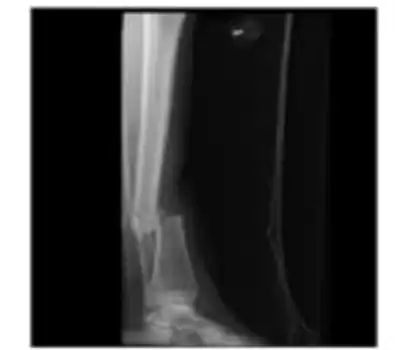

Open fracture of the shaft of the tibia.

X-ray of tibia shaft fracture

Anteroposterior (AP) and lateral radiographs the include the entire length of the lower leg (knee to ankle) are highly sensitive and specific for tibial shaft fractures.[4]